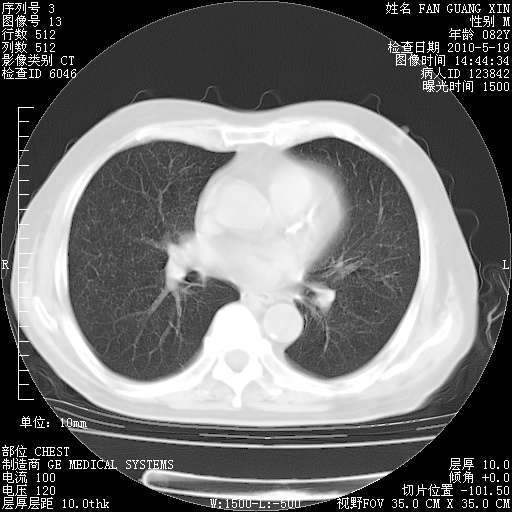

复查肺部CT,明显好转。为什么发热呢?

治疗3周后的肺部CT

治疗3周后的肺部CT纵隔窗